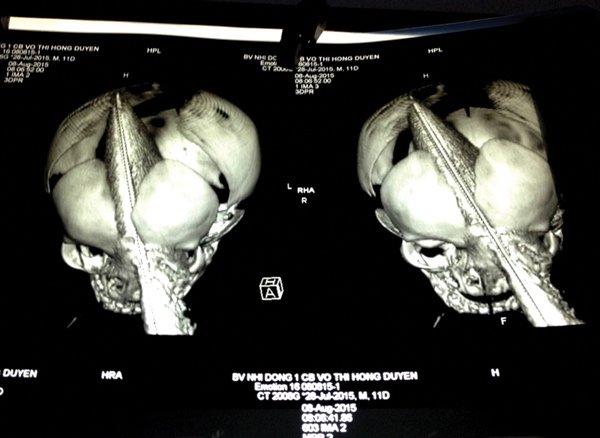

Hình ảnh chẩn đoán lúc bé nhập viện với con dao xuyên sọ

“Khi đến nơi, dù da vẫn còn hồng nhưng bé đã mê man, con dao vẫn còn cắm sâu. Thăm khám cho thấy bé bị rỉ máu mang tai và đỉnh đầu, vết thương thấu sọ. Con dao dài 28cm, phần thân dao 18cm và phần cắm vào 11cm”, bác sĩ Tâm kể.

ThS.BS. Đào Trung Hiếu, Phó giám đốc BV. Nhi Đồng 1, người trực tiếp thực hiện ca mổ cấp cứu cho biết vết thương xuyên từ thành trong hốc mắt trái, chệch hướng lên xuyên não phía phải. Lưỡi dao xuyên gần hết vào não. Đây là lần đầu trong đời làm bác sĩ, ông tiếp nhận trường hợp bé sơ sinh bị đâm xuyên sọ nghiêm trọng như vậy.